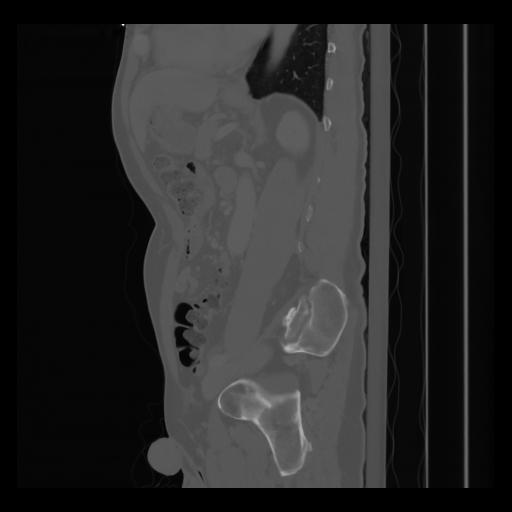

36 CUERPO,CE,Sagittal,3.000,CUERPO,Sagittal,